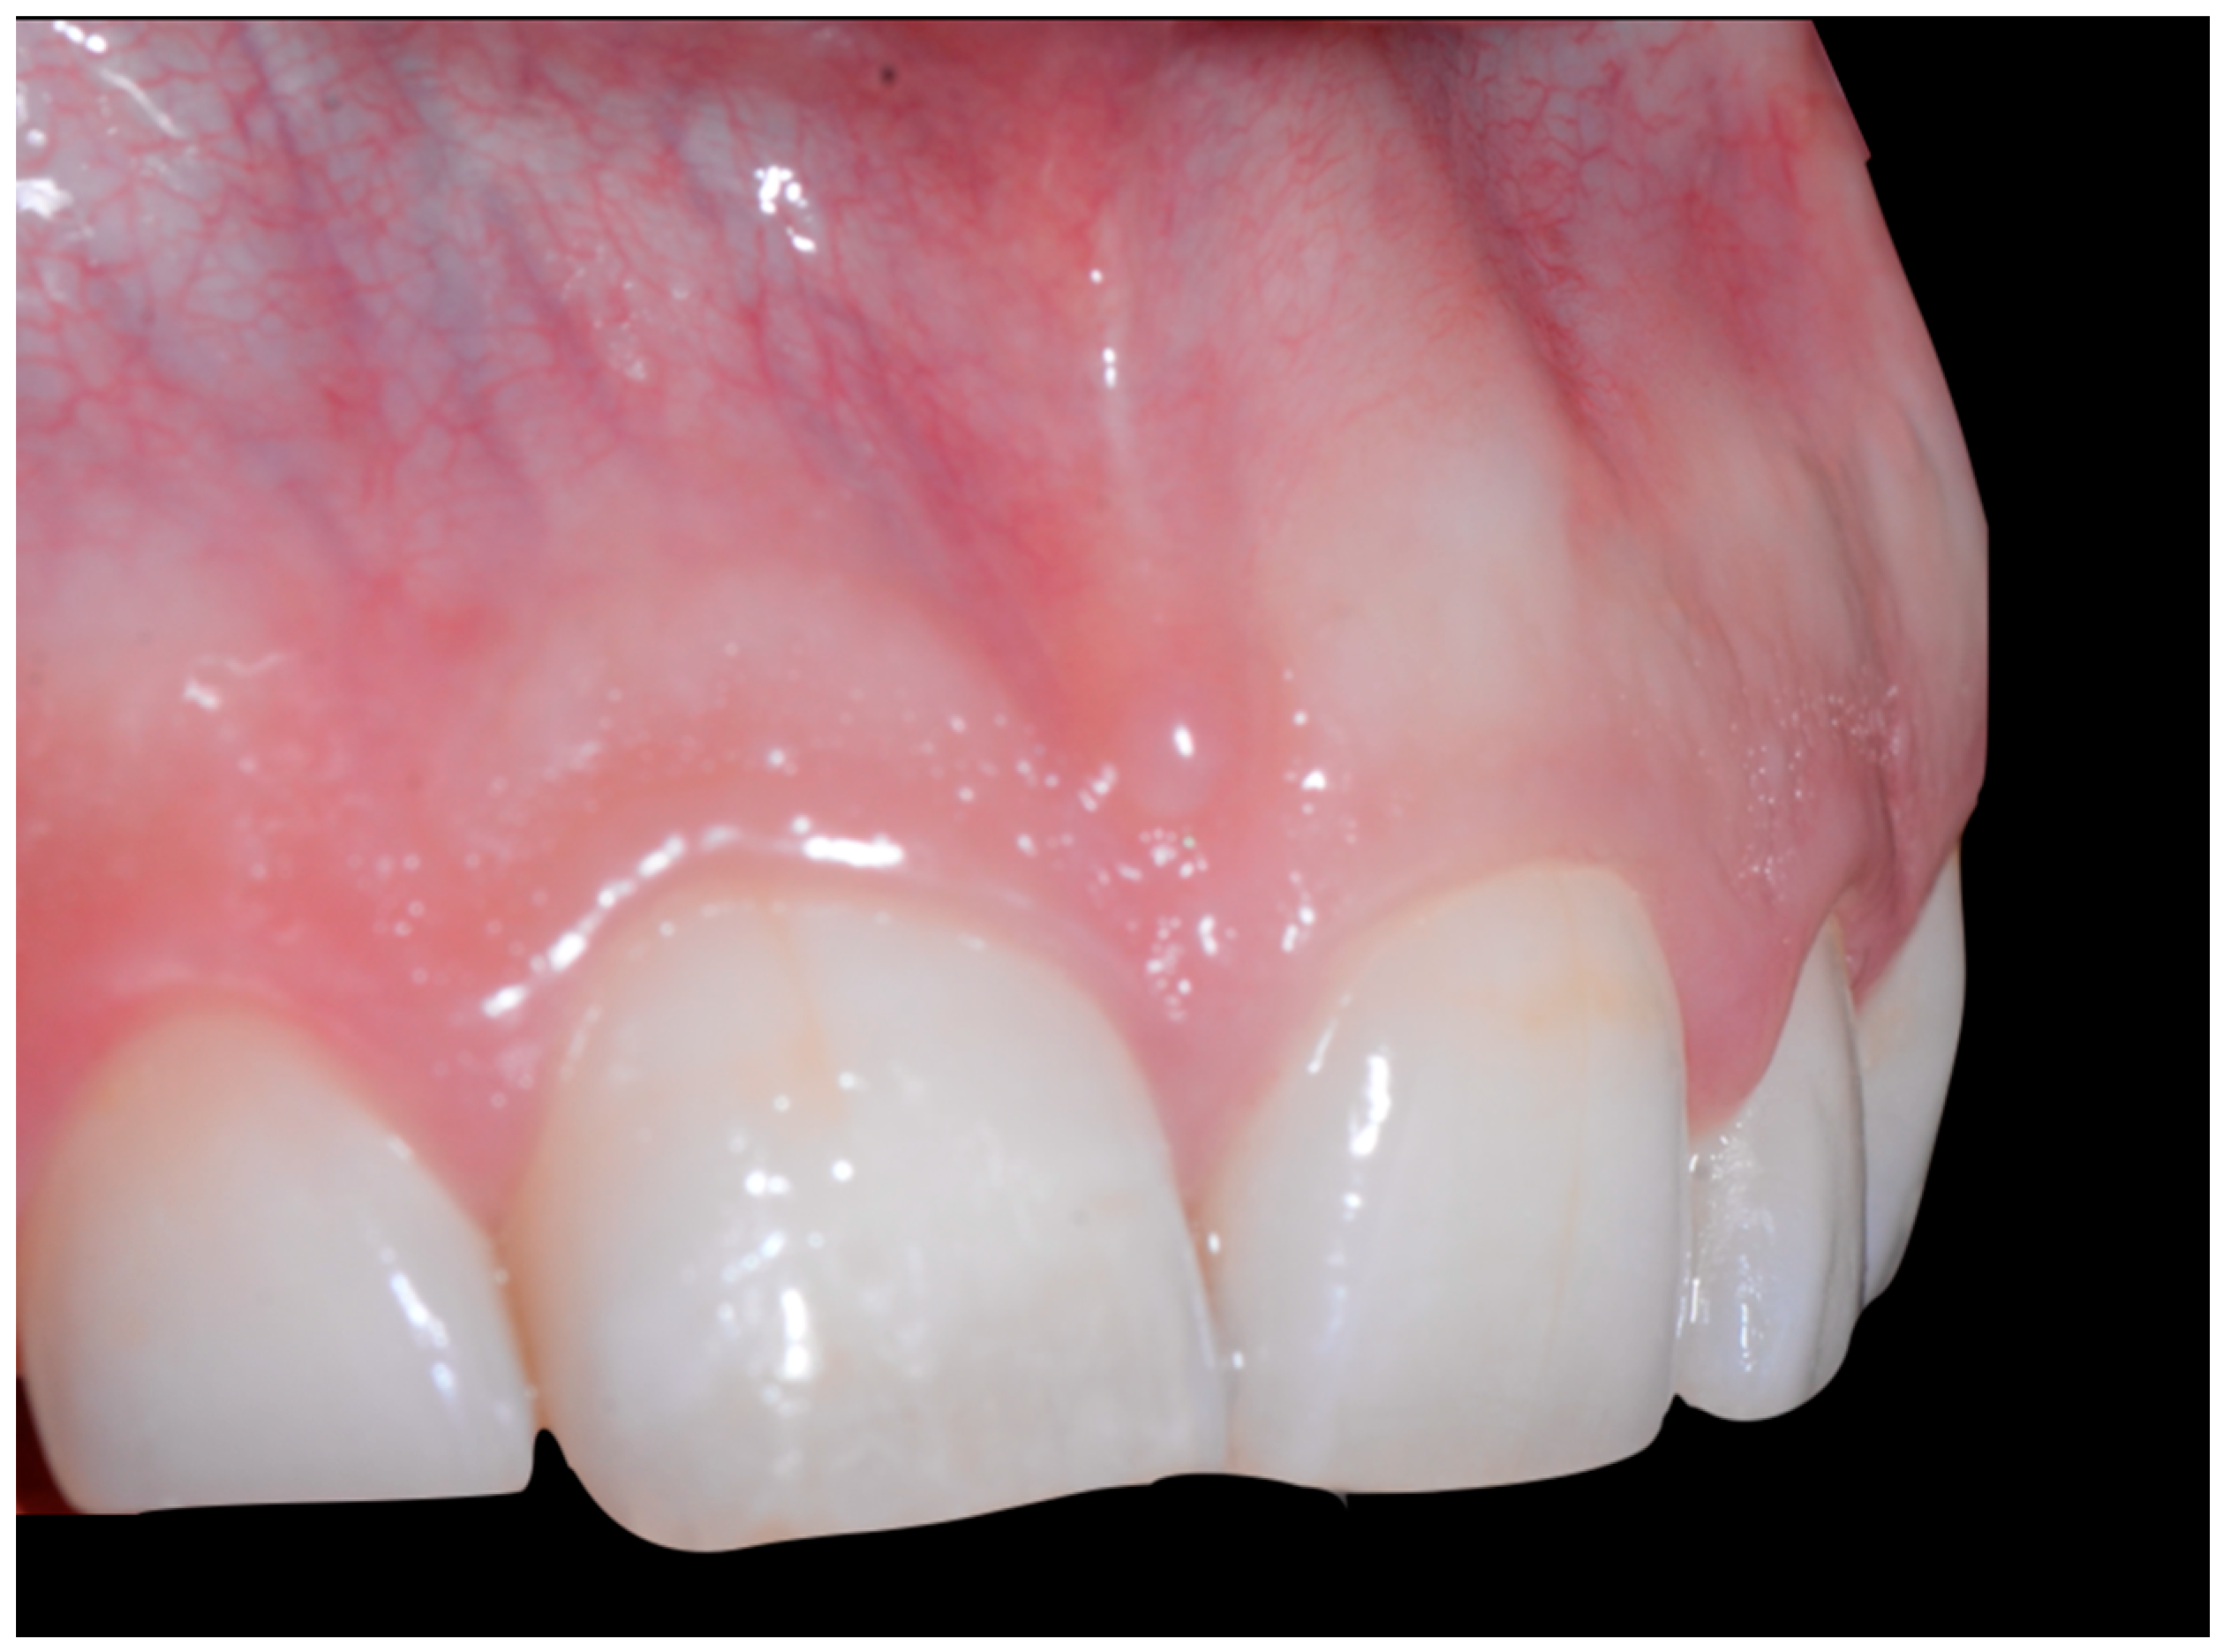

In Figure 6, 11 and 21 show a difference in incisal edge height and gingival margin. Tooth 41 shows gingival recession to the muco-gingival junction (Cairo’s RT1) with root visibility. Tooth 33 had a significant lingual tilt (coronal–lingual torque), not symmetrical to tooth 43.

Intermediate wire syndrome. Frontal view.

The root of tooth 21 is visible through the gingiva (Figure 7). Figure 8 shows the extent of gingival recession on tooth 41.

Intermediate wire syndrome. Lateral view.

Intermediate wire syndrome. Lateral views.